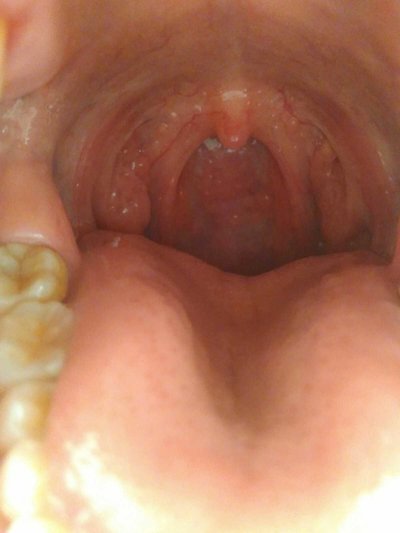

Wind heat cough: frequent and severe cough, coarse breath or hoarse cough, white or yellow mucus spitting, accompanied by yellow nose, sore throat, thirst and headache. Optional drugs: Jizhi syrup, Chuanbei Pipa syrup, Xiaoer Feire Kechuan oral liquid.